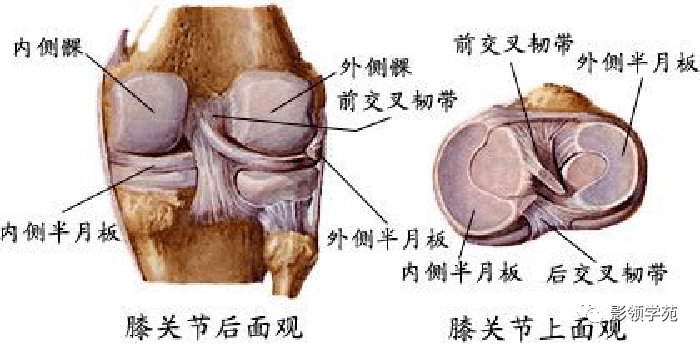

关节与韧带系统

韧带系统

关节与韧带系统

韧带系统